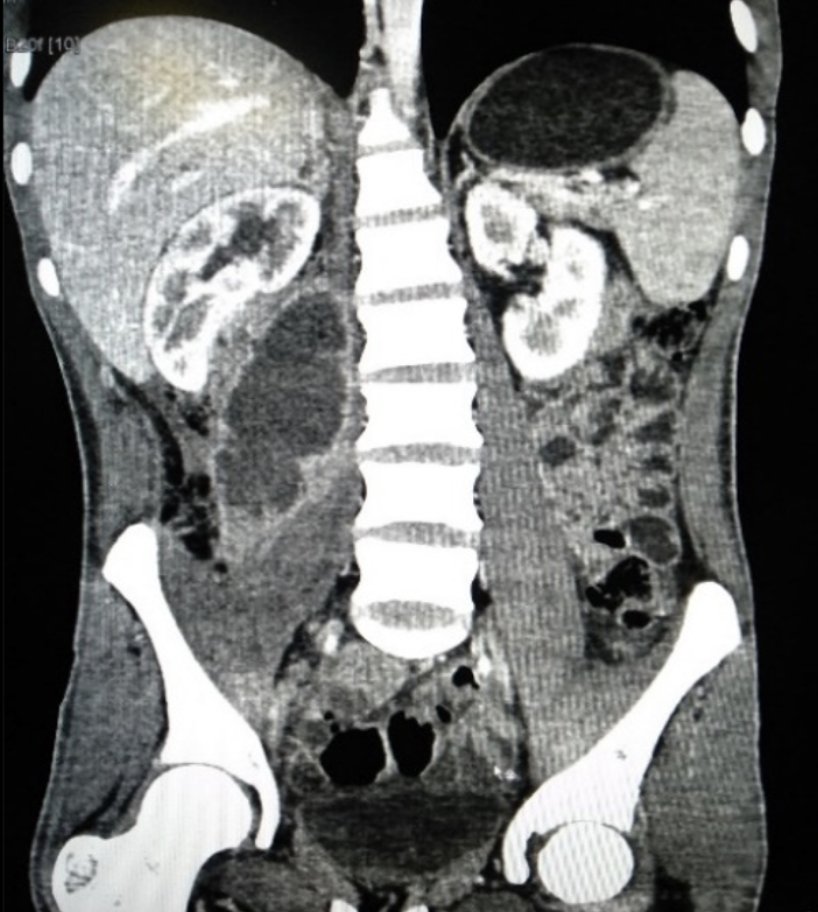

Pain caused by hip flexion/extension + ring enhancing mass in pic: - Psoas abscess! MCC = S. aureus (TB or Salmonella if from discitis) Tx: Abx + Percutaneous drainage or open surgical drainage (if from perforated bowel) if > 7cm HPI usually includes IVDU/DM/Immunosuppressed